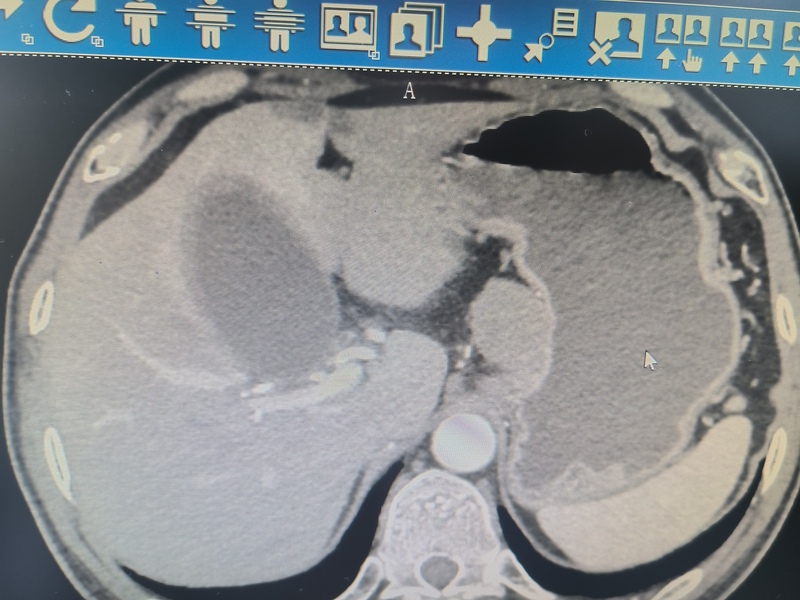

诊断方法包括内镜检查、影像学检查,如CT扫描、超声内镜、MRI检查。增强CT为GIST的首选检查方法,直肠间质瘤推荐MRI作为首选的检查方法。

影像学测量肿瘤大小可作为简单的危险度评价标准。一般胃部5cm为界,小肠以3cm为界,此外,肿瘤黏膜面溃疡、内部坏死、形状不规则、边缘模糊浸润、供血/引流血管扩张、邻近脏器侵犯常提示为高危限度影像征象。